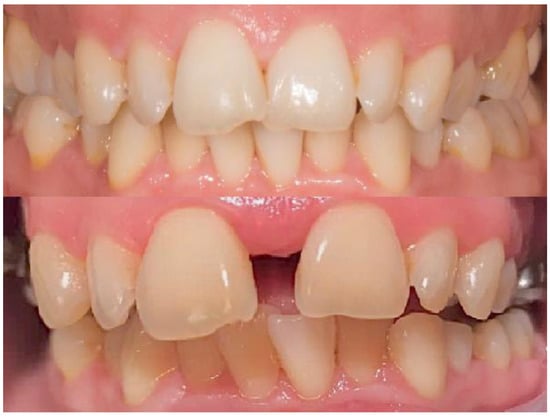

| Data | Canine Inclination/° |

|---|---|

| Mean | 4.10 |

| 25% Percentile | 2.783 |

| Median | 3.21 |

| 75% Percentile | 3.865 |

| Maximum | 4.77 |

| Mean | 4.103 |

| Std. Deviation | 0.3881 |

| Std. Error of Mean | 0.08679 |

| Lower 95% CI of mean | 2.921 |

| Upper 95% CI of mean | 3.784 |